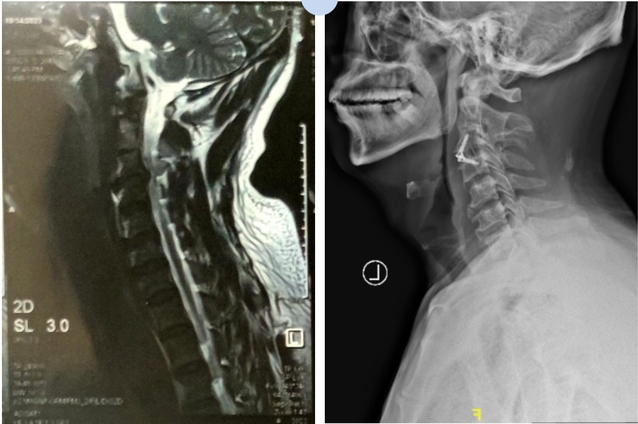

病例二

巨大的突出物已切除,椎间隙高度恢复,椎管容积扩大,神经压迫解除,双手麻木感消失。